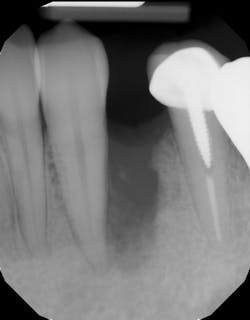

Although unpredictable, a greater amount of alveolar ridge loss following extraction usually occurs in the horizontal dimension and affects the buccal bone of the ridge.3 In fact, 50% of alveolar bone dimension can be lost after tooth extraction, with losses reported of up to 6–7 mm (figure 1). Two-thirds of this loss of bone volume can occur within the first three months of tooth extraction.4